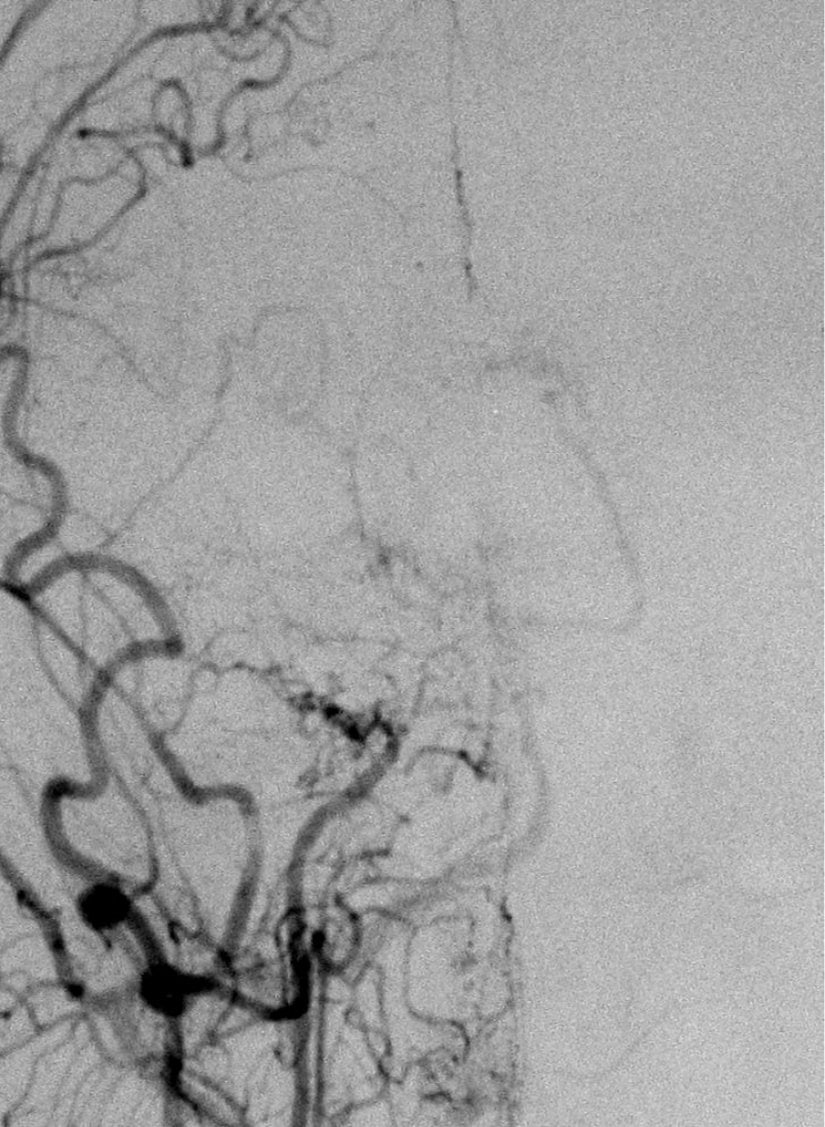

Moyamoya hastalığının teşhisi, nadir görülmesi ve bariz olmayan belirti ve semptomlardan dolayı zor olabilir. Teşhis, klinik bulgular ve görüntüleme bulguları temelinde şüphelenilerek konur. Teşhisin doğrulanması için standart yöntem serebral anjiyografi olarak kabul edilir.[7]

Serebral anjiyografi, moyamoya hastalığını doğrulamak için kullanılan standart bir yöntemdir. İşlem sırasında, kontrast madde enjeksiyonu ile beyin damarlarının röntgen filmi çekilir. Ancak, bu yöntem intravenöz kontrast kullanımına bağlı alerjik reaksiyonlar ve nadiren kontrast maddeye bağlı böbrek hasarı gibi riskleri içerebilir.[7]

Tanıda etkili olan bir diğer unsur, hastanın klinik belirtileri ve görüntüleme bulgularıdır. Moyamoya hastalığının belirgin bulguları genellikle supraclinoid iç karotis arterleri ve bunların proksimal dallarını içerir.[7]

Etimoloji

Japonca'da "havada dağılan sigara dumanı" anlamına gelen ve "moyamoya" şeklinde telaffuz edilen "もやもや" terimi, hastalığın anjiyografik görünümünden esinlenmiştir.[1], [2], [5], [8]